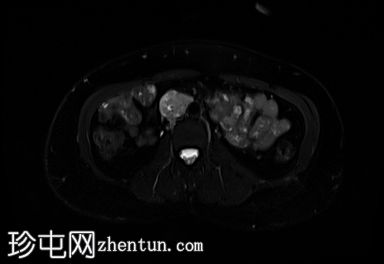

轴位

DWI

右侧腹膜后可见一边界清晰的肿块,位于主动脉分叉上方。

病灶大小约为3.5 x 3.0 x 4.1 cm(前后径 x 横径 x 头尾径)。

T2加权像显示异质性高信号,DWI/ADC显示明显扩散受限,增强后明显强化。

对下腔静脉有轻微压迫,无直接侵犯或血栓形成的证据。

病灶旁可见两个小的、不规则的淋巴结,疑似转移。